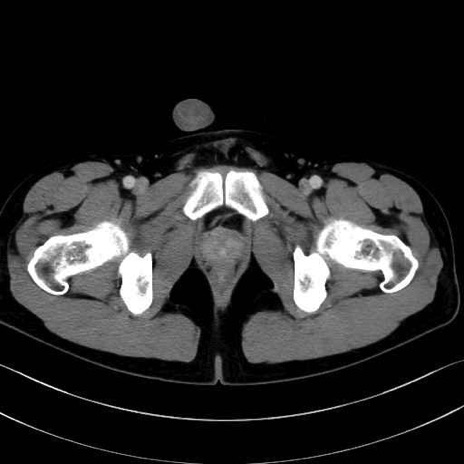

精嚢(seminal vesicle)のCT画像における解剖

症例

【症例】20歳代 男性 スクリーニング